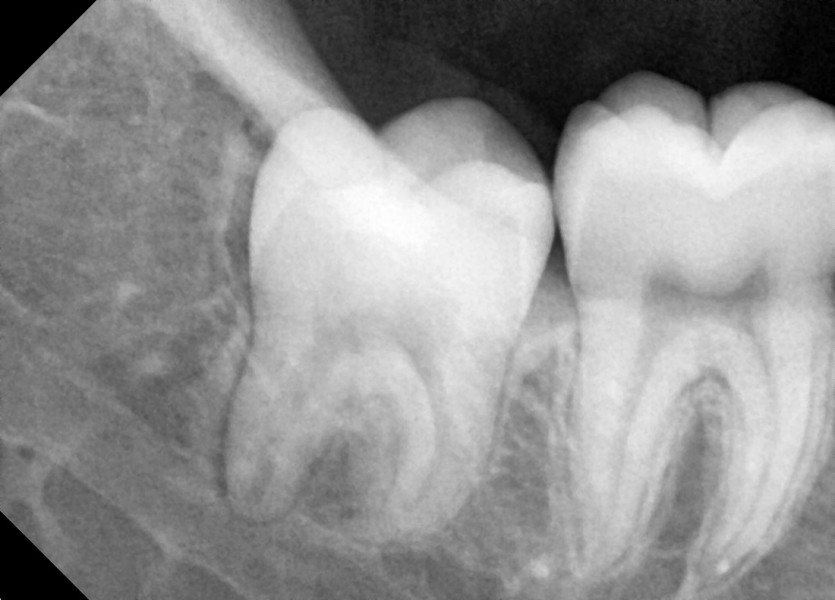

#18,48 사랑니 발치

구강외과 전문의가 당일 발치했습니다.